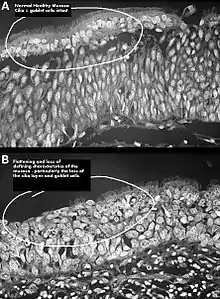

There are no objective physical examination findings that definitely diagnose ENS.[1] Generally, one or more turbinates may be reduced or absent when viewed in medical imaging or via endoscope with no sign of physical obstruction, the mucosa will be dry and pale, and there may be signs of secondary infection.[1]